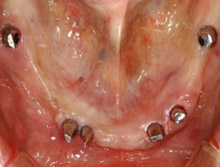

この症例は、すべての歯を失った口腔内をインプラントで治療した例です。

治療前のパノラマエックス線写真。歯がほとんど残っていませんし、残っている歯もほとんど使えません。

治療前口腔内。残っている下の前歯は重度歯周病で揺れています。審美と機能の改善を患者さんは希望されました。

術前の上顎

術前の下顎

上顎は4本のインプラントを植立し、義歯タイプの補綴物をいれます。

下顎は6本のインプラント植立し、ブリッジタイプの補綴をいれます。